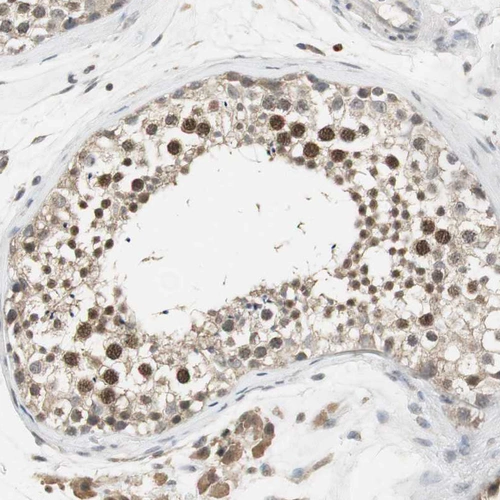

Immunohistochemical staining of human testis shows strong nuclear positivity in cells in seminiferous ducts.